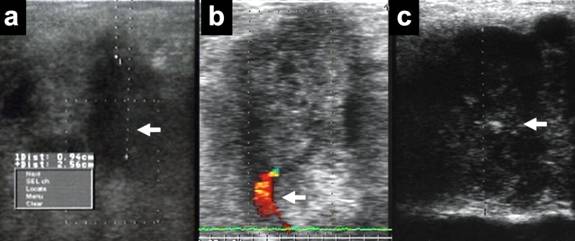

LUS-guided CNB was performed using an 18-gauge needle that was introduced through the right anterior abdominal wall above the pancreatic tumor (Figure 1). Tumors with cystic components were excluded to avoid the risk of peritoneal dissemination resulting from needle puncture. Before the CNB, we dissected a part of the omentum and opened the omental bursa using two laparoscopic dissectors through 5-mm working ports to observe the distal pancreas and directly puncture the tumors. All punctures were performed several times under LUS from a laparoscopic view. Ultrasonographic procedures consisted of the following three steps: (1) measurement of tumor location and size, (2) a search for critical vessels around the tumor using Doppler mode, and (3) a confirmation of safe puncture sites in the tumor (Figure 2). If critical vessels crossed the puncture line, we aborted the biopsy and later switched to EUS-FNA. The obtained tissue samples were used for frozen sections and the final pathological diagnosis (Figure 3). Immediate LUS-guided CNB-related complications were recorded during the procedure, and patients were monitored for late complications (>24 h postoperatively) before discharge. Umbilical open wounds were sutured with absorbable sutures.

Figure 2. Laparoscopic ultrasonographic images during the puncture of the pancreatic tumor. a. The dotted line indicates the pre-puncture path through the tumor. b. The identification of critical vessels using color Doppler imaging around the tumor. c. The white arrow indicates the needle puncturing the tumor. |